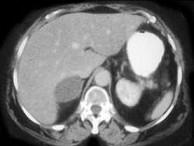

问题 女,45岁,满月脸、向心性肥胖2年余,实验室检查:血、尿皮质醇增高,请结合CT图像,作出诊断 ( )

选项 A、左肾上腺嗜铬细胞瘤 B、左肾上腺增生 C、左肾上腺腺癌 D、左肾上腺转移瘤 E、左肾上腺腺瘤

答案 E